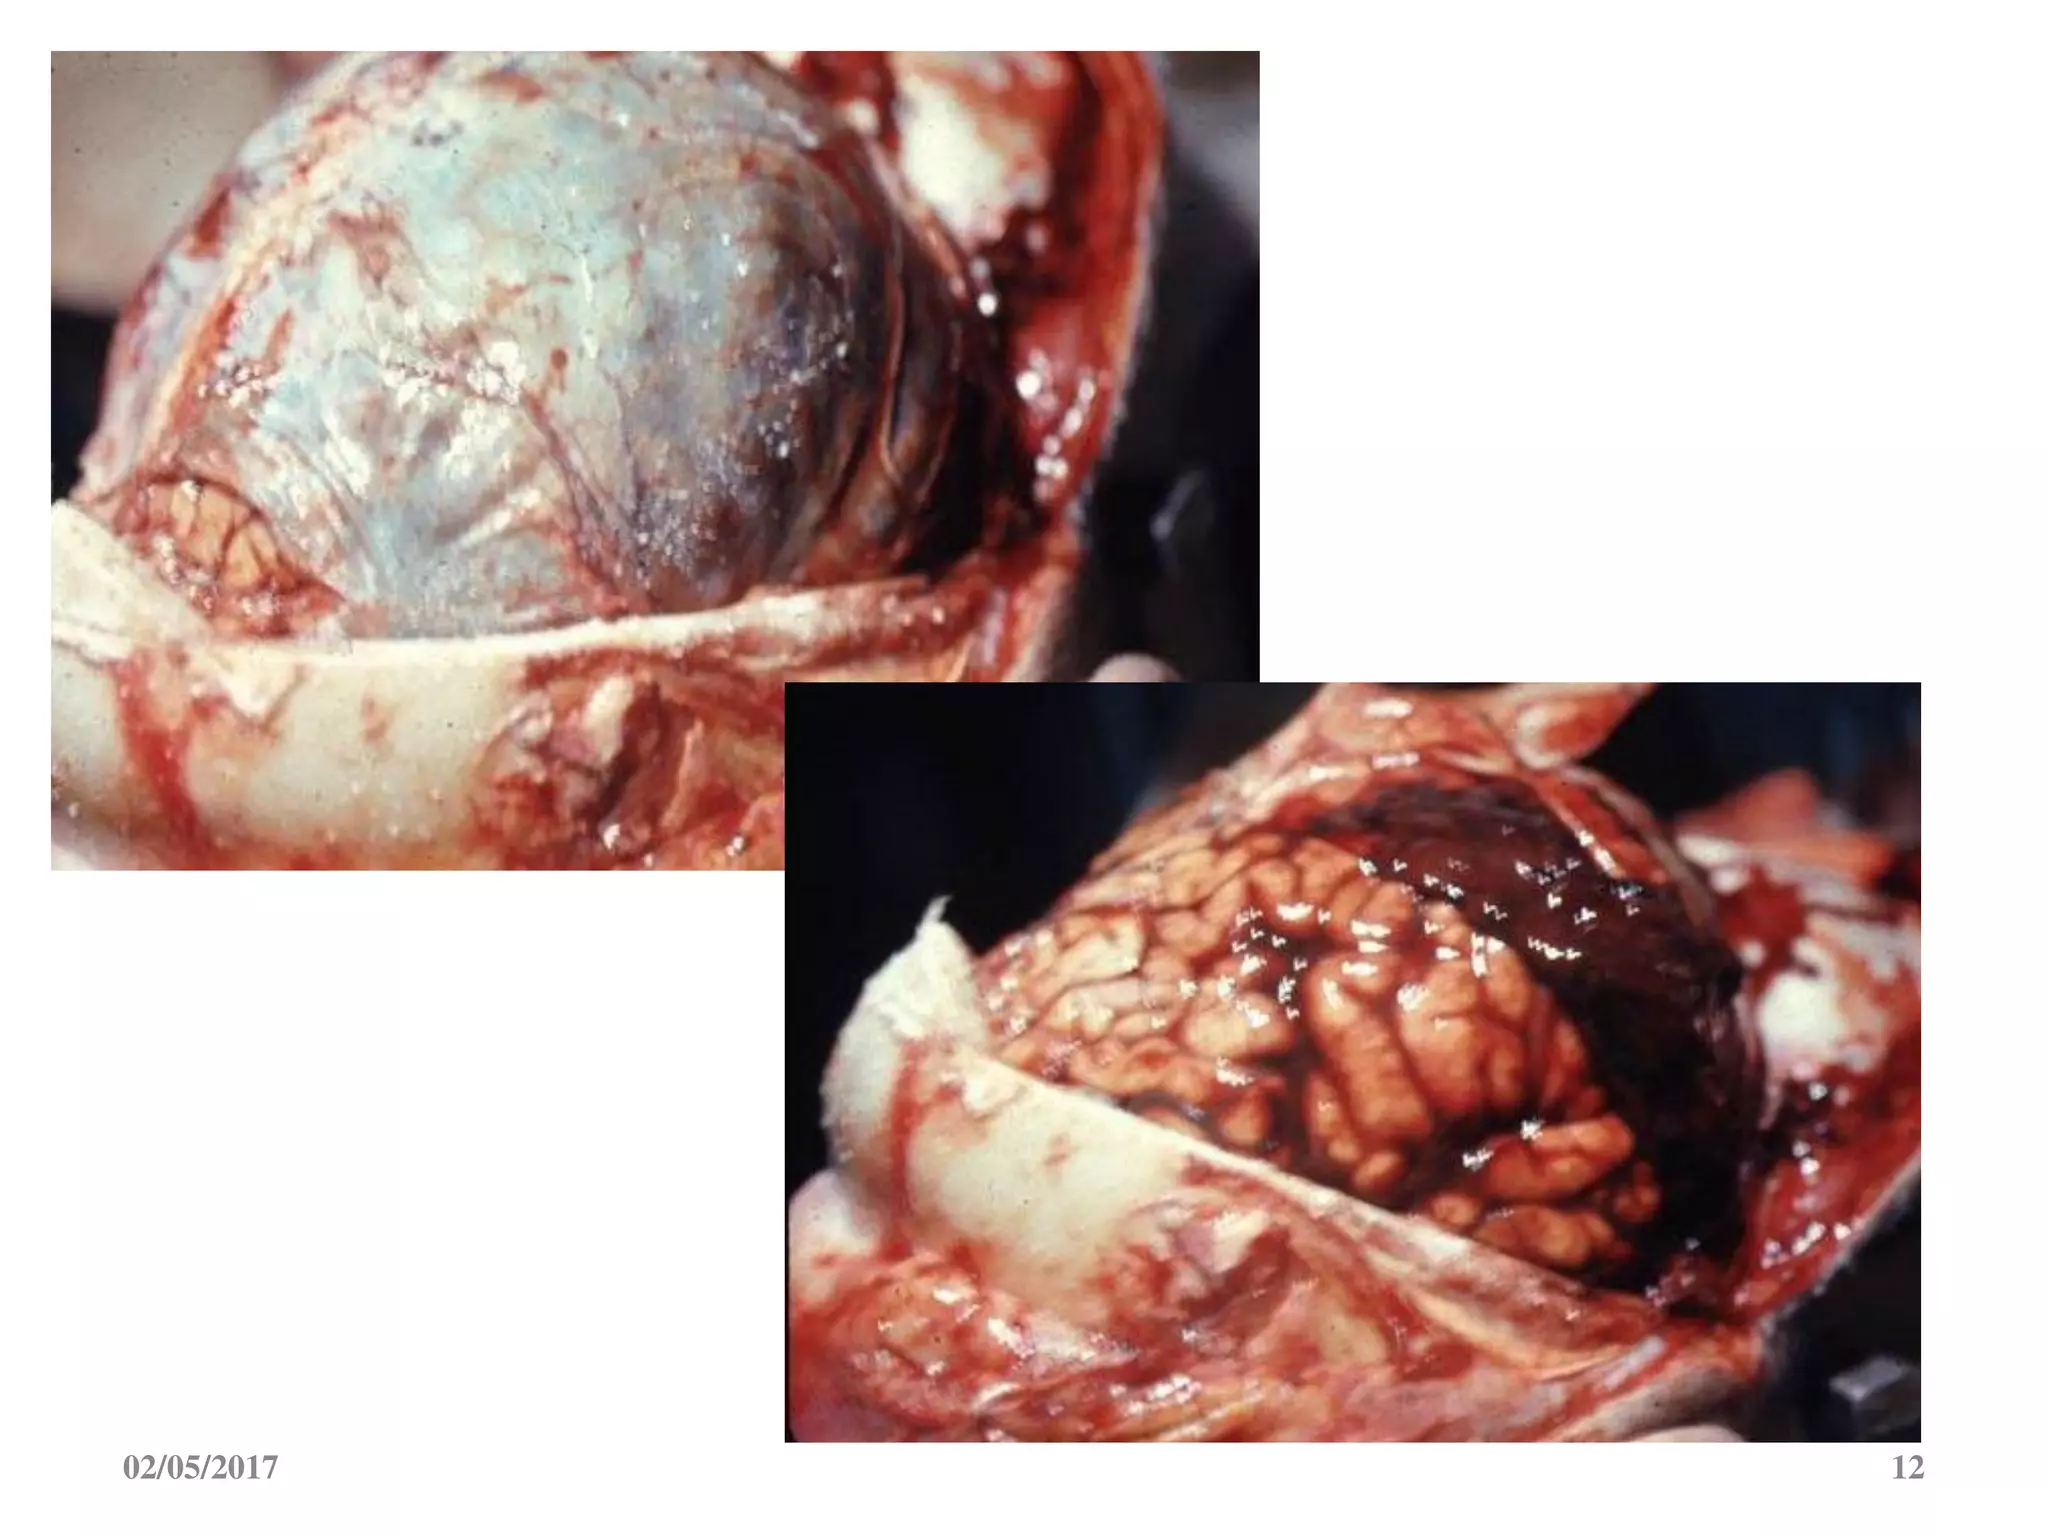

8. MAÙU TUÏ DÖÔÙI MAØNG CÖÙNG

- Maùu tuï naèm giöõa maët trong

maøng cöùng vaø voõ naõo

- Thöôøng do raùch caùc tónh maïch

caàu noái

02/05/2017 12